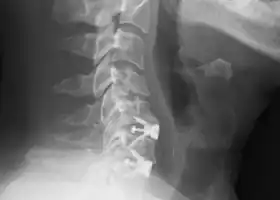

![]() X-rays of anterior cervical discectomy and fusion, C5C6 and C6C7. Lateral view. | |

The neurosurgeon or orthopedic surgeon enters the space between two discs through a small incision in front (= anterior) of and at the right or left side of the neck. The disc is completely removed, as well as arthritic bone spurs. The disc material, pressing on the spinal nerve or spinal cord, is then completely removed. The intervertebral foramen, the bone channel through which the spinal nerve runs, is then enlarged with a drill giving the nerve more room to exit the spinal canal.

To prevent the vertebrae from collapsing and to increase stability, the open space is often filled with a graft. That can be a bone graft, taken from the pelvis or cadaveric bone; or an artificial implant.[4] The slow process of the bone graft joining the vertebrae together is called "fusion". Sometimes a titanium plate is screwed on the vertebrae or screws are used between the vertebrae to increase stability during fusion, especially when there is more than one disc involved.